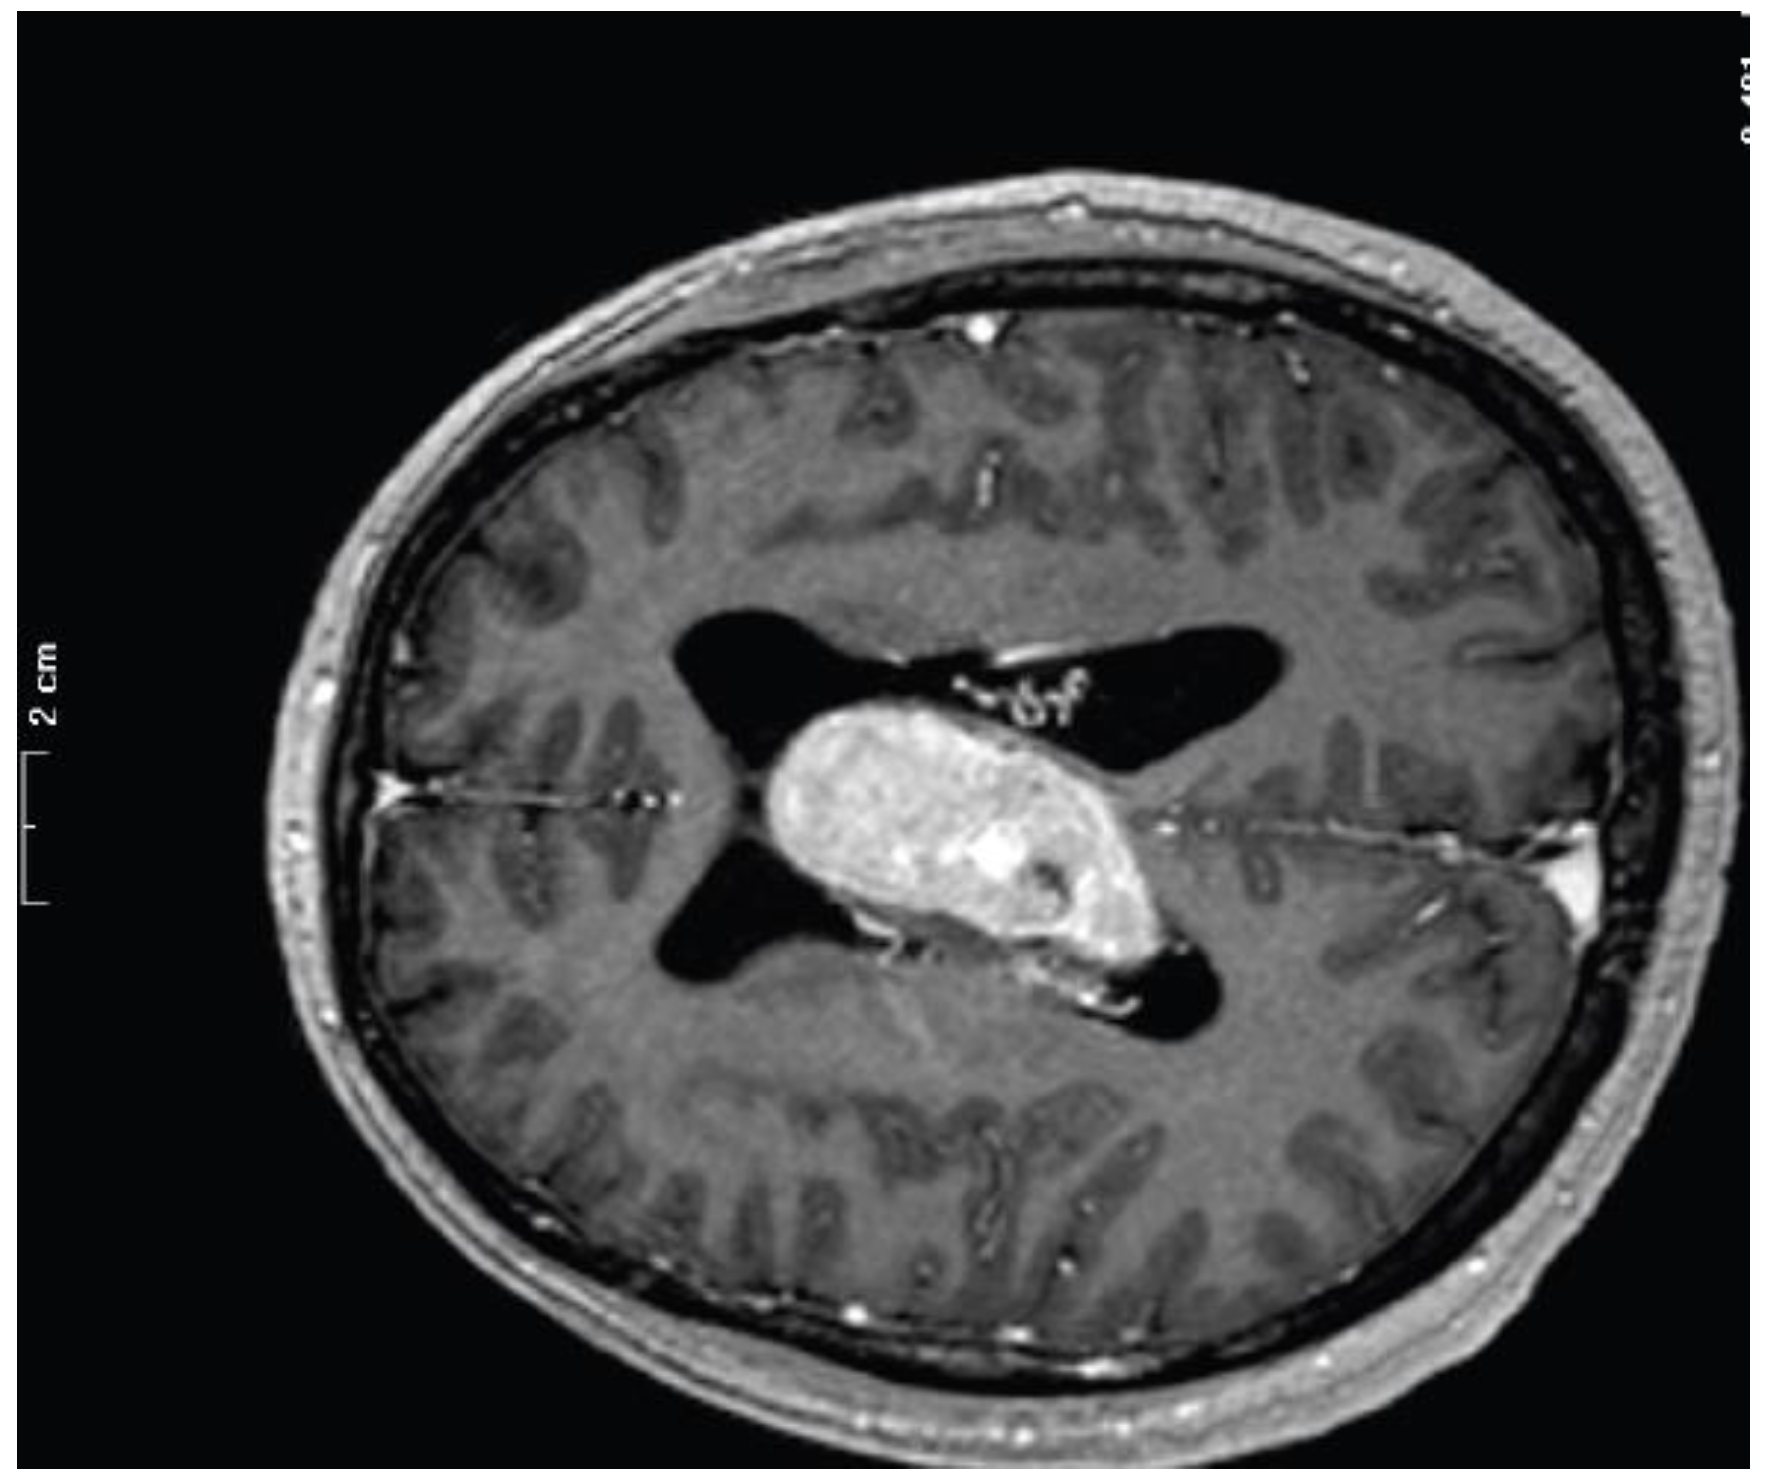

| Case | Age | Sex | Site | Surgery | Histotype | Post-Surgical Complications | Adjuvant Treatment | Recurrence (RFS) | TMB (muts/Mb) |

|---|---|---|---|---|---|---|---|---|---|

| 23M | 45 | M | III, LV, RV | Partial | meningothelial | respiratory failure, hydrocephalus, and surgical site infection | GK | no (40) | 1.87 |

| 24M | 47 | F | LV | Total | transitional | none | None | no (48) | 5.13 |

| 25M | 25 | F | RV | Total | transitional | pneumatocephalus | None | no (12) | 0.87 |

| 26M | 70 | M | RV | Total | transitional | pneumatocephalus | None | no (72) | 0.86 |

| 27M | 66 | M | LV | Total | transitional | hematoma in surgical site | None | not available | 1.71 |

| 28M | 31 | F | LV | Total | atypical | none | None | no (7) | 2.28 |